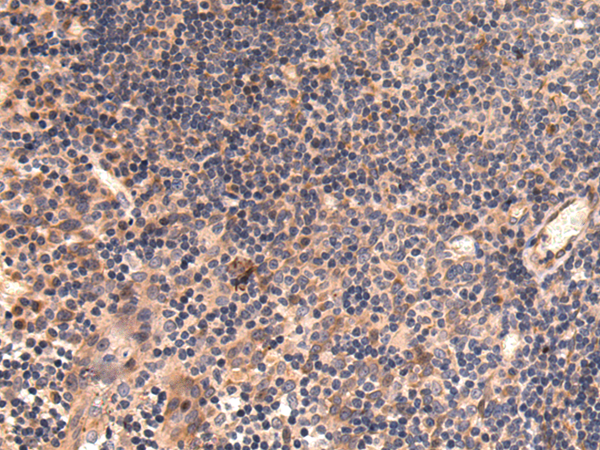

分类: 科研抗体货号: P08417别名: C11; CDR; DD4; CHDR; DD-4; HAKRA; 3-alpha-HSD应用: WB,IHC反应种属: Human